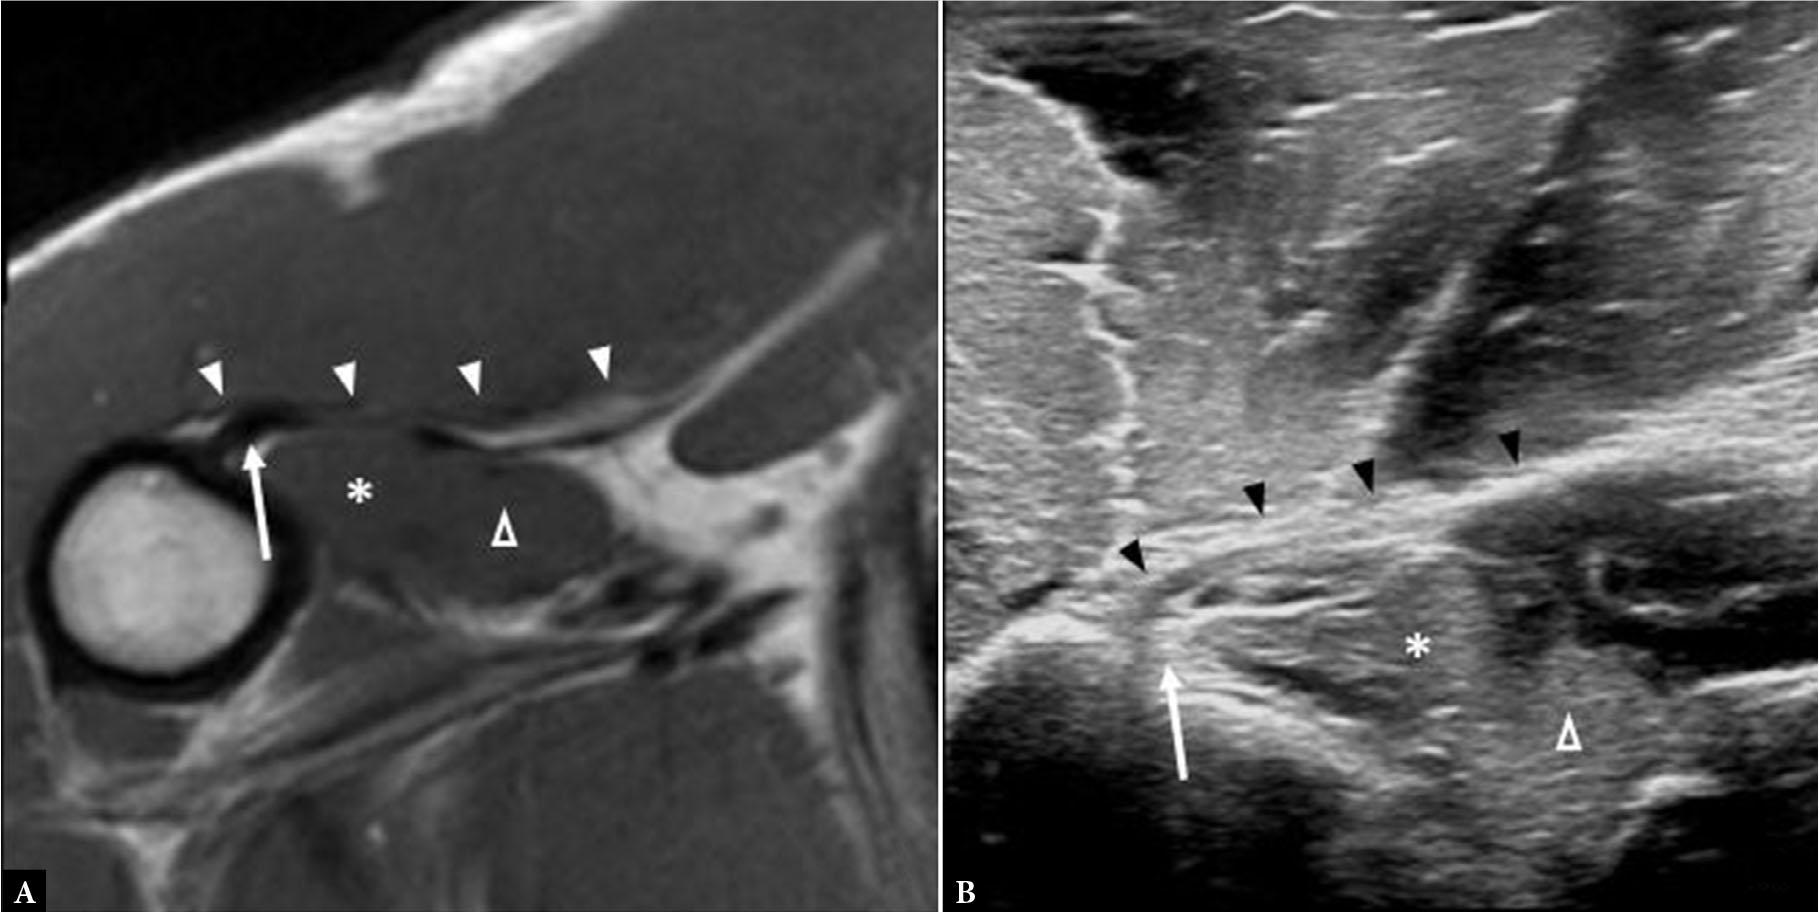

Fig. 8.

A. Long axis gray scale ultrasound images (A and B) and short axis fluid-sensitive MR image (C) show complete tear of the PM tendon with residual tendon stump (arrowheads) attached to the humerus and hematoma formation (asterisk)

Muscle fiber and tendon disorganization, laxity and/or focal defect are characteristic imaging findings of acute PM tear (Fig. 7, Fig. 8, Fig. 9, Fig. 10). In the acute phase, this manifests as a focal T2 hyperintense or hypo/anechoic abnormality within the substance of the muscle or tendon on MRI and US, respectively.

Hematoma formation is a secondary sign of injury and can be within the muscle or tissues surrounding the torn tendon (Fig. 7, Fig. 8).

Acute hematoma demonstrates fluid signal on MRI and is predominately hypoechoic on US(12). In the subacute and chronic phases, hematoma can appear more organized and anechoic on US and, depending on chronicity, shows variable signal intensity on MRI(12).